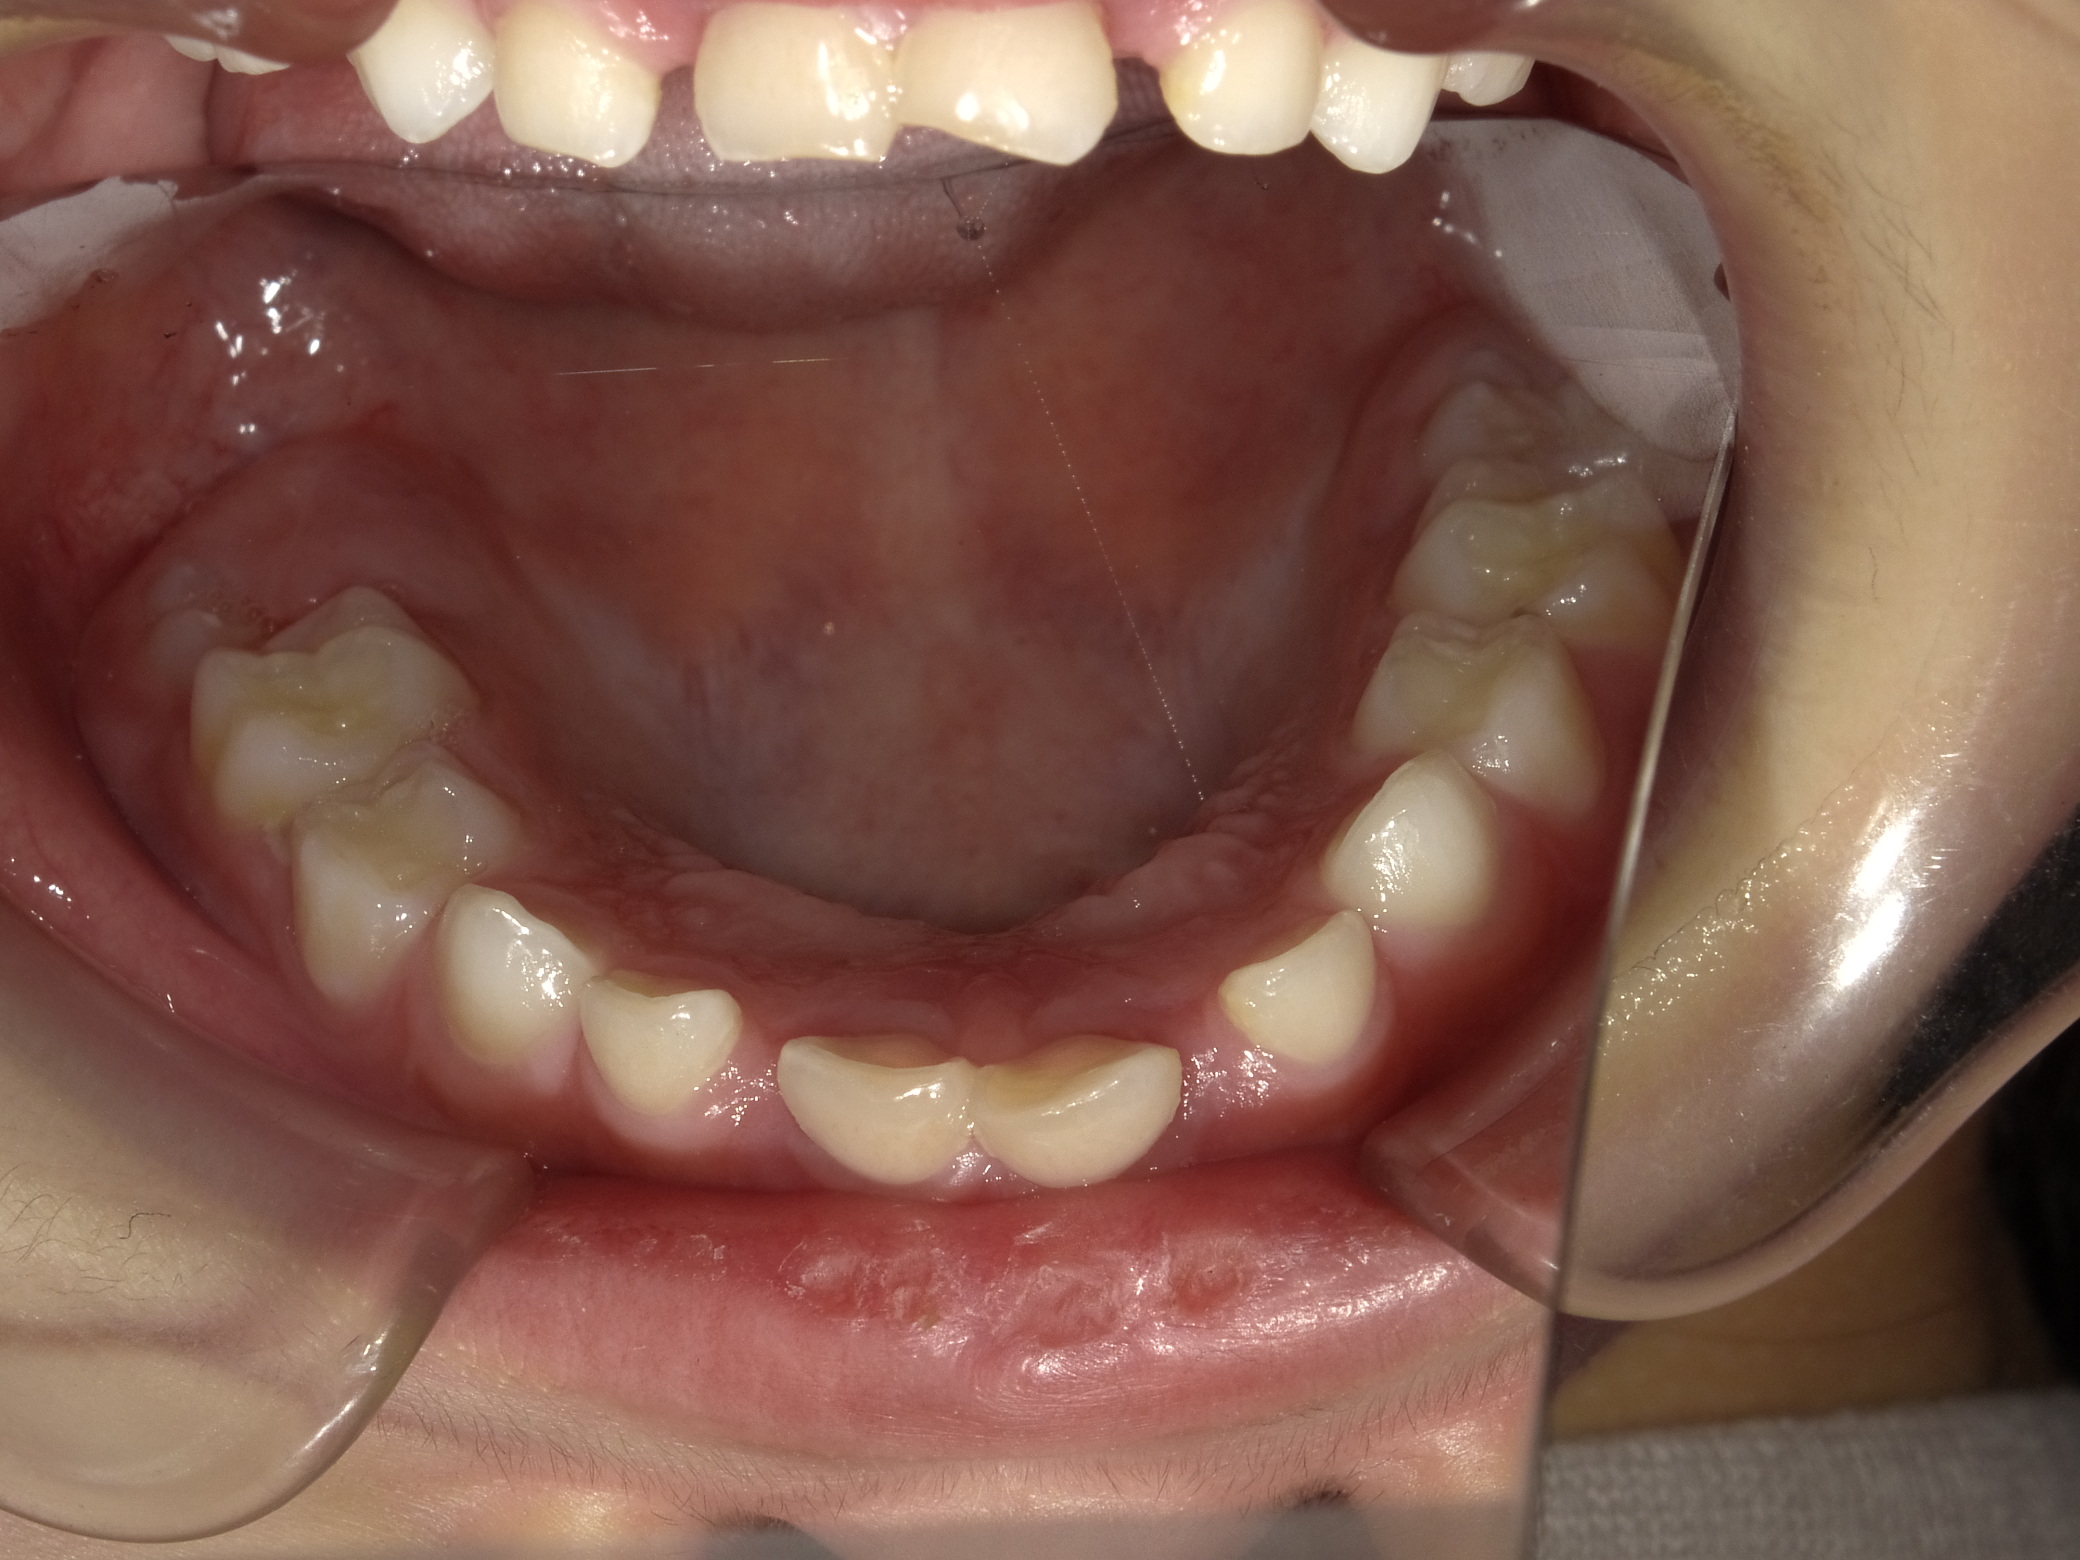

下顎